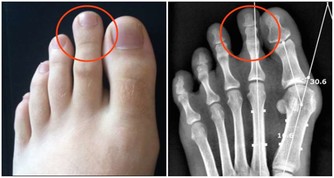

2. 牙周疾病。牙垢久積,容易形成牙結石,牙石的存在會妨礙口腔衛生,促使菌斑更多地形成,

牙石本身也會吸附更多的細菌和毒素,造成牙齦充血、水腫,產生牙齦炎、牙周炎等問題;

3. 牙齒深層問題。隨著牙齦炎向深層組織發展,甚至會導致牙齦自發性出血、口腔異味、牙槽骨破壞、牙齒鬆動等問題。